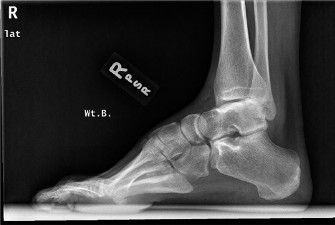

A 16-year-old male presents noting frequent sprains to his right ankle. He notes that he rolls his right ankl…